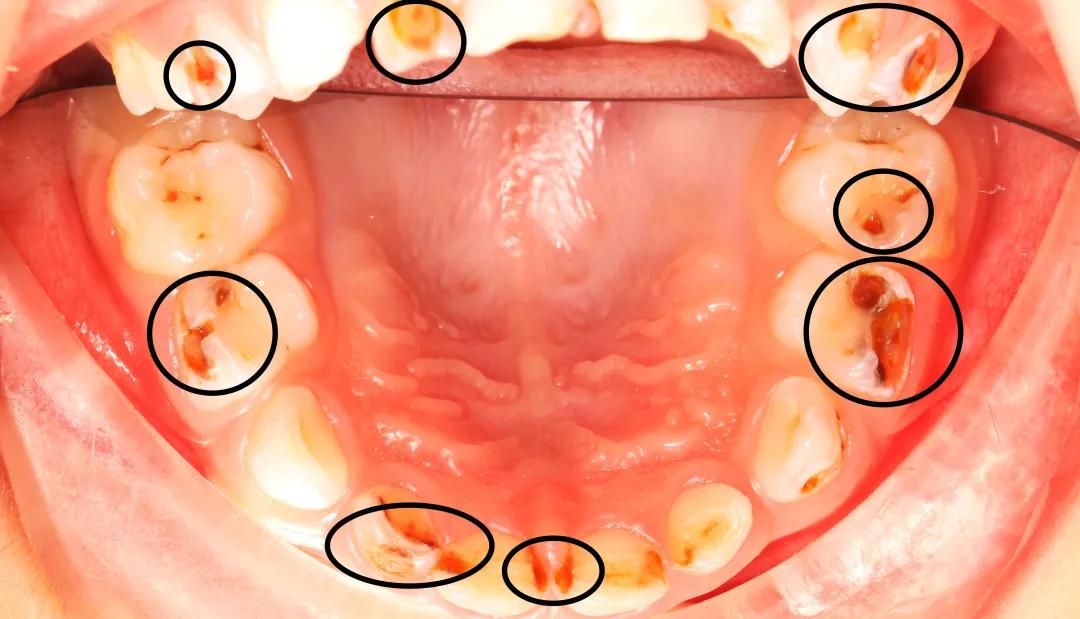

△密密麻麻的小黑牙和洞洞△

童童乳牙蛀了17颗,任其发展下去,势必影响恒牙的萌出,还可能导致营养不良。